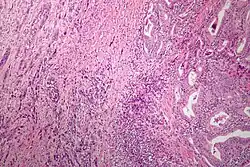

Microscopic image of anaplastic thyroid carcinoma. H&E stain.

Anaplastic tumors have a high mitotic rate and frequently invades the local blood and lymphatic vessels.[5] Cellular death is frequently visualized on microscopic images.[2] The presence of regionally swollen lymph nodes in older patients in whom needle aspiration biopsy reveals characteristic vesicular appearance of the nuclei supports a diagnosis of anaplastic carcinoma. Microscopic images of ATC usually show inflammatory cells from the immune system such as T cells and macrophages.[2]

On immunohistochemistry testing, ATC is usually positive for the keratin, p53, and PAX8 proteins and is negative for thyroid transcription factor-1, thyroglobulin, and calcitonin.[2] ATC cells demonstrate high levels of PD-L1 expression.[2] BRAF and TERT mutations are seen more commonly in ATC than in differentiated thyroid cancer.[2]